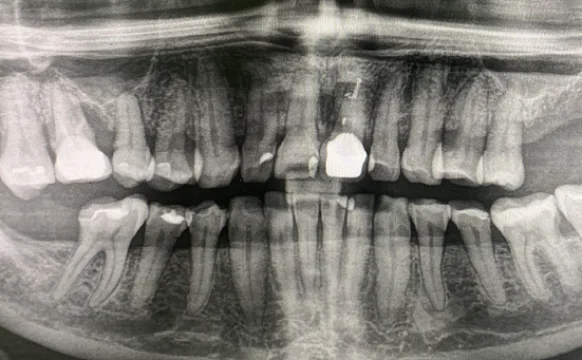

Имплантация Straumann

Проблема

отсутствие зуба

Врач

Мамедов Эльшан Мехманович